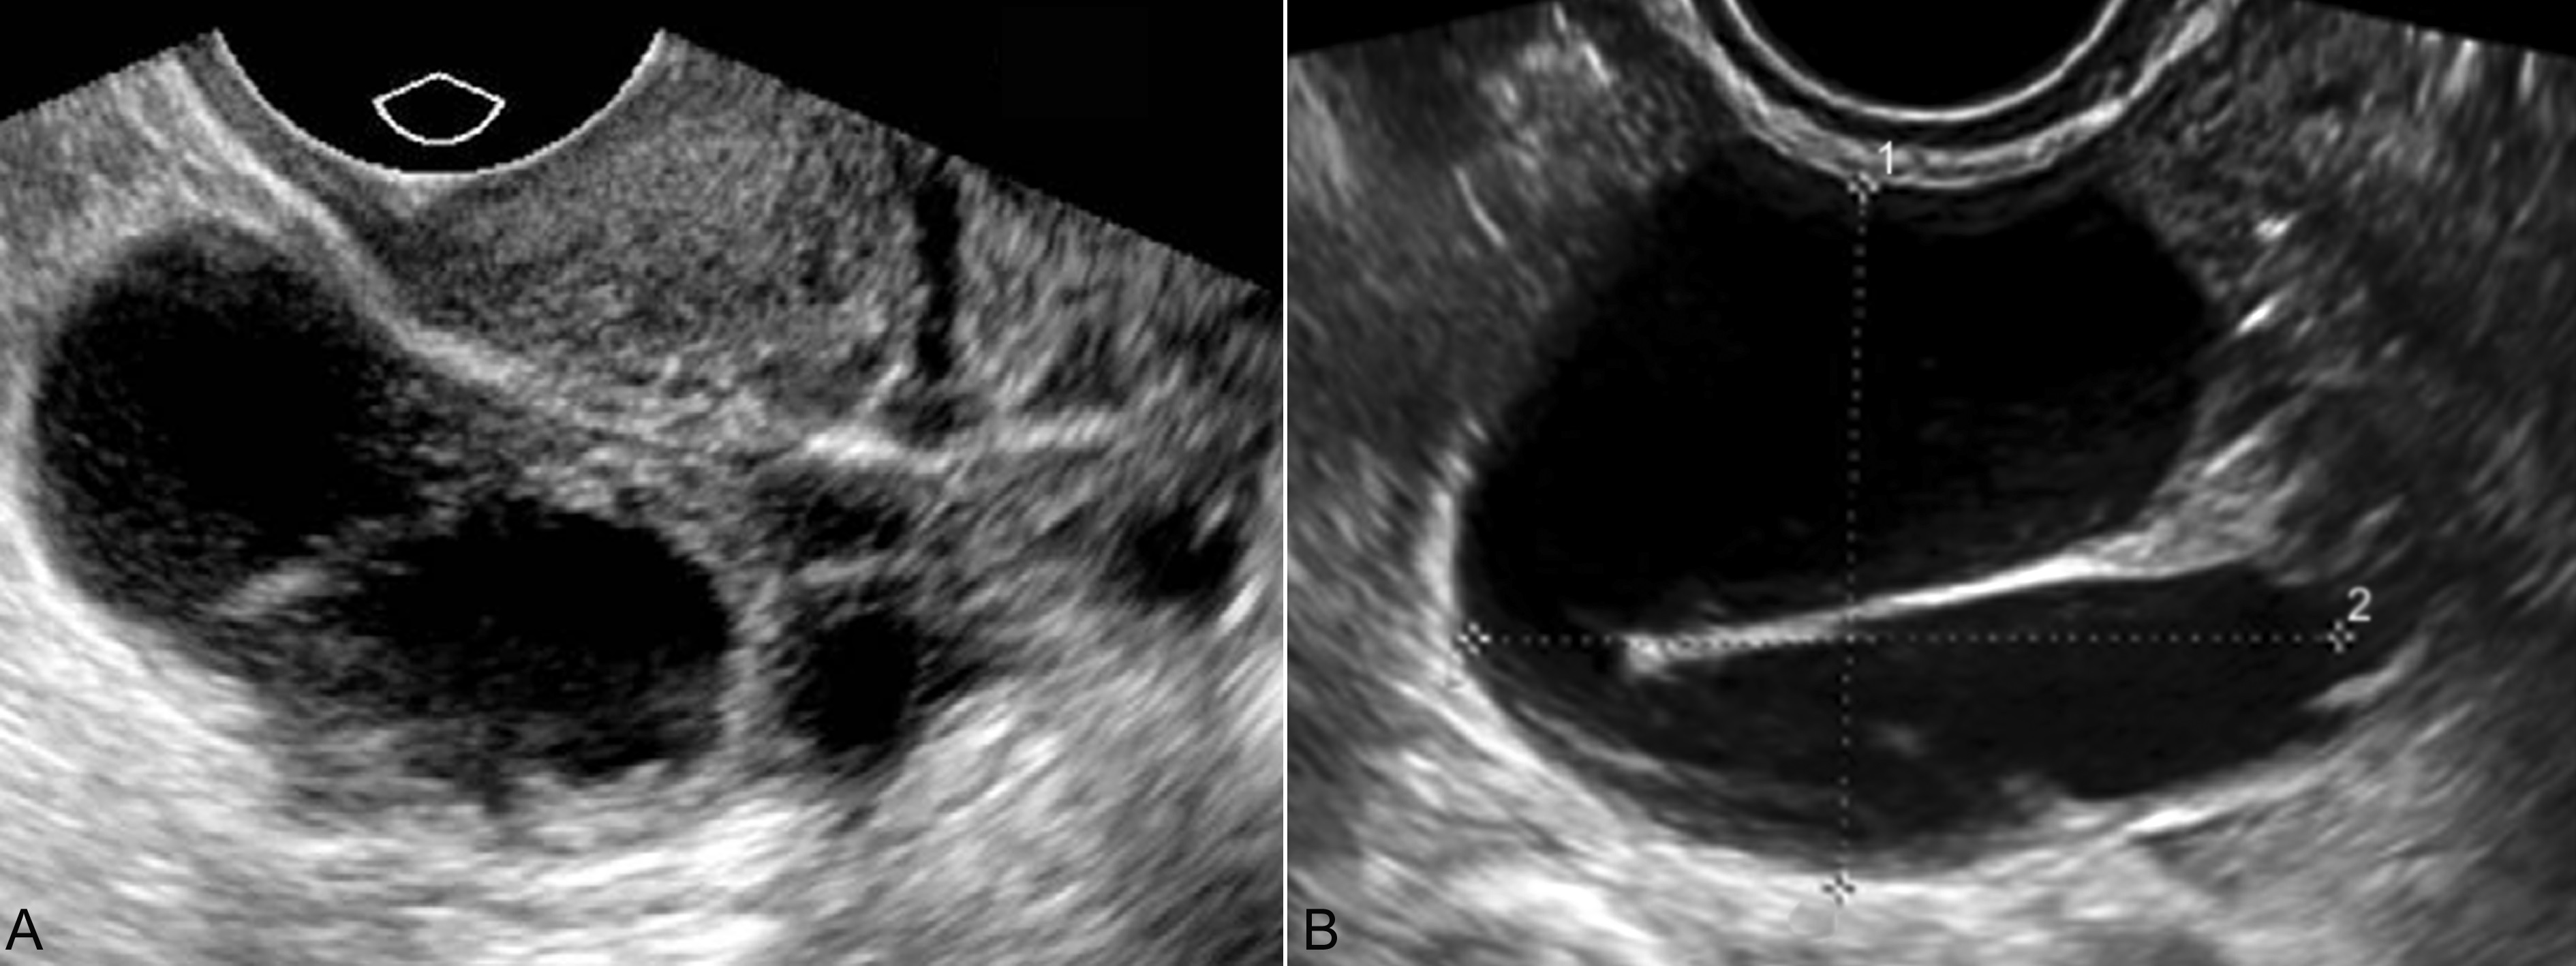

输卵管积液(sactosalpinx)是盆腔内炎症的后遗症。由于盆腔炎症可以影响精子和卵子的运行而影响怀孕,一般不会与妊娠并发或可能成为异位妊娠的诱因。很少的情况下可以有单侧输卵管积液和妊娠并发。多数输卵管积液较轻,妊娠早期超声显象检查显示为子宫旁的梭形无回声结构,内侧起源于子宫角部,形态规则,边缘多显示清晰,壁较厚,内部透声良好;明显的输卵管积液可显示为腊肠样或迂曲的管状无回声区(图1),以至于超声显像检查与卵巢其他囊性病变不易区别;中晚期妊娠后超声检查多难以显示和诊断本病。

图1输卵管积液声像图

A:子宫一侧显示腊肠样输卵管积液的无回声内部并点状低回声,边缘模糊,周围显示不均匀型炎性低回声

B:另一病例,子宫一侧显示迂曲输卵管积液无回声